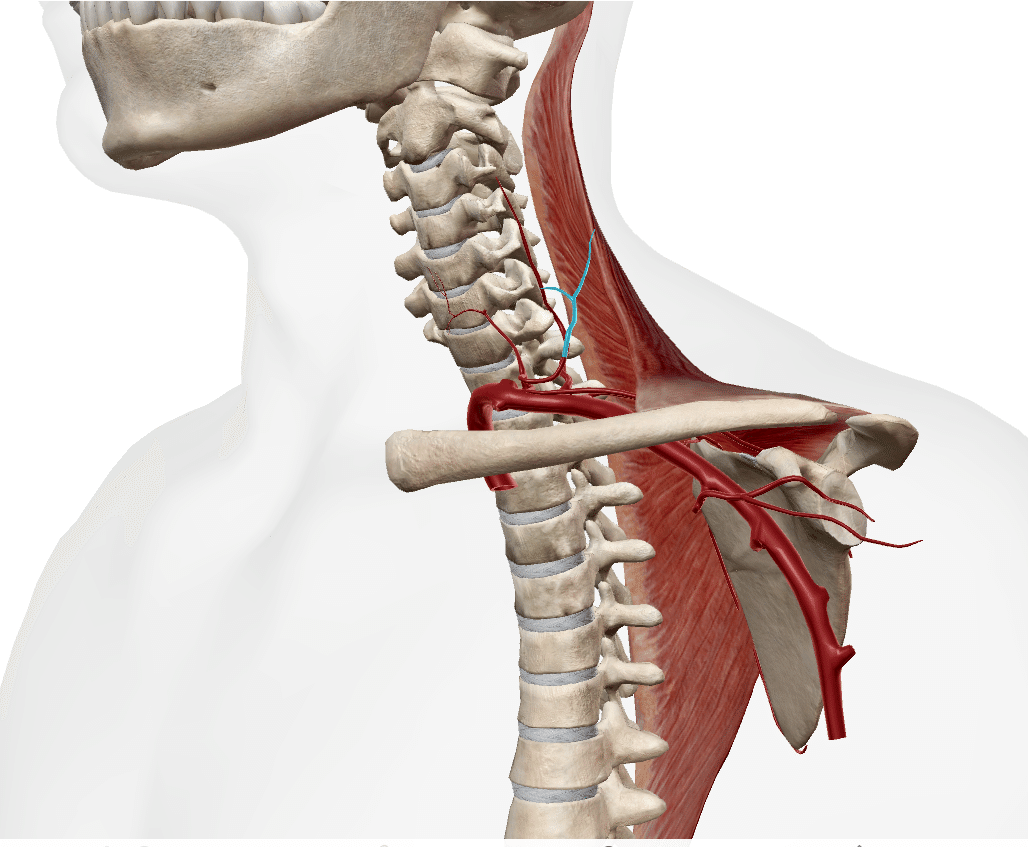

支配神経

副神経(CN11)

頚神経叢

(C3・C4)

(引用:同上)

血液供給

頚横動脈